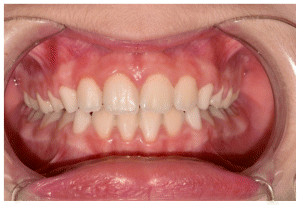

The patient was a young female presenting with a Class III dento-skeletal malocclusion, which was treated using the AMCOP® TC appliance. A comprehensive diagnostic protocol was carried out both before and after treatment, including orthopantomography (Figure 2–3), postero-anterior teleradiography (Figures 4, 5), latero-lateral cephalometric radiography (Figures 6, 7), cephalometric analysis (Tables 1, 2), as well as extraoral (Figures 8, 9) and intraoral photographs (Figures 10, 11). The extraoral examination revealed an edge-to-edge incisal relationship and the presence of a midline diastema. Pre-treatment cephalometric analysis (Deltadent® Lana, Bolzano, Italy) confirmed the diagnosis of a skeletal Class III malocclusion. The treatment plan involved the use of the AMCOP® TC appliance. The patient was instructed to wear the device for two hours in the afternoon and throughout the night for the first six months, followed by nighttime use only for an additional six months. Upon completion of the treatment, the patient achieved a Class I occlusion, with correction of both overjet and overbite. Additionally, the device facilitated tongue re-education and contributed to the postural realignment of the first cervical vertebra.